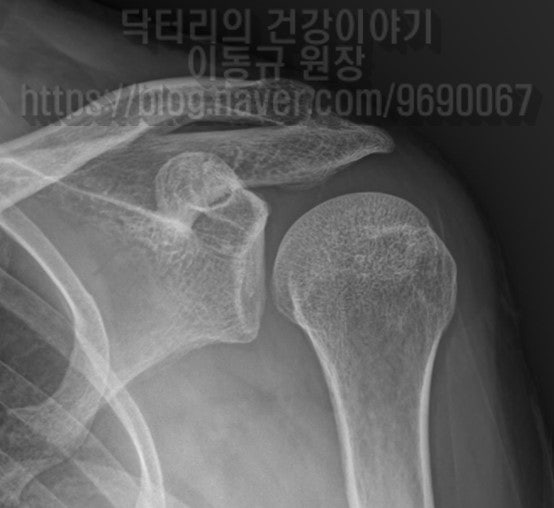

안녕하세요. 정형외과 전문의 이동규 원장입니다. 오늘은 잘못된 진단으로 잘못된 치료를 받아 고생하다 저한테 오신 분을 소개해 드리려 합니다. 48세 여자 환자 분으로 2개월전 넘어지면서 좌측 어깨 통증 및 움직임 제한을 주소로 내원하신 분입니다. 환자는 타원에서 MRI 검사까지 받고 난 후 염좌 및 타박을 진단받고 약물 및 물리치료, 도수치료만 해오셨다고 합니다. 그럼에도 불구하고 통증은 지속되고 점점더 증상이 악화되어서 저한테 내원하셨던 분입니다. 이학적 검사상 impingement sign 양성 보였으며 apprehansion test, relocation test 양성 소견이 보였습니다. 무슨 의미냐 하면 어깨 탈구가 의심되는 소견입니다. 가지고 내원하신 자료를 살펴 보도록 하겠습니다. X-ray 를 보면